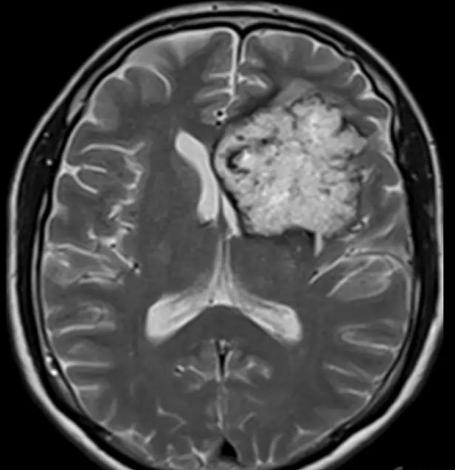

答案:血管型脑膜瘤。血管型脑膜瘤是一种比较罕见的脑膜瘤类型,脑膜瘤在所有的颅脑部位肿瘤中占到五分之一左右。WHO(2016)中枢神经系统肿瘤分类中把脑膜瘤分成15个亚型,血管瘤型脑膜瘤是其中一个亚型,属于WHOⅠ级肿瘤。临床症状取决于病变部位、大小及周围水肿情况,常以头痛、恶心、呕吐等颅内高压为主要表现。血管瘤型脑膜瘤是富血供肿瘤,病理上瘤内血管成分较多,表现为管径不一的血管瘤结构或高度扩张的薄壁海绵状血管瘤结构,均为分化成熟的血管。血管型脑膜瘤影像表现既有一般脑膜瘤的常见表现,又有自身特点。

1)肿瘤密度及信号:血管型脑膜瘤CT平扫多呈低密度,MRI扫描T1WI呈低信号,T2WI呈高信号,T2WI信号强度高于其他亚型。

2)肿瘤内血管。血管型脑膜瘤血供非常丰富,CT及MRI可见多发增粗或留空的血管影,增强扫描显著强化。有文献提出瘤内出现血管留空信号时血管型脑膜瘤的特征性表现。而“烟花征”也可认为时血管型脑膜瘤的特征性表现。

烟花征

3)肿瘤内坏死、囊变、出血及钙化少见。

4)瘤周水肿。常见病理类型的脑膜瘤瘤周一般水肿较轻或无水肿,这是脑膜瘤区别于其他脑肿瘤的一个征象,但血管型脑膜瘤瘤周水肿发生概率较其他病理类型高。

图1 T2WI呈高信号图。图2MRI增强扫描明显、均匀强化,肿块周围脑实质见大片水肿